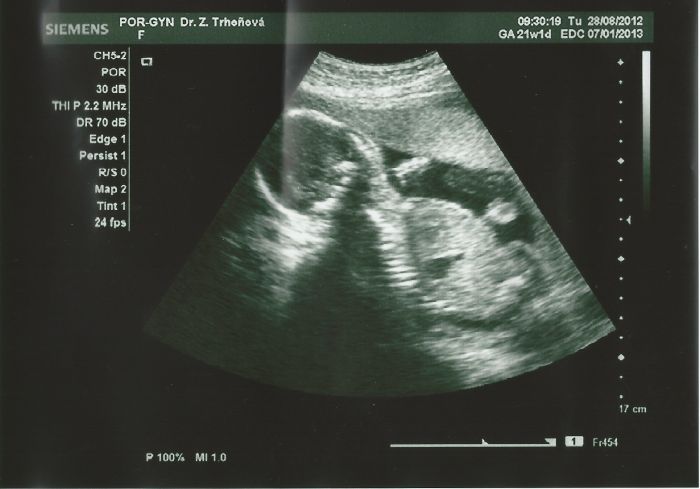

Přikládám slibované,ale bohužel nezřetelné snímečky, maličká je po ránu pěkná čiperka a je moc rychlá :-))

A uvidíte důkaz té naší svalovkyně :-))

1. fotka - je její svalnaté kopýtko :-)) ( asi z toho kopaní, kope jako das :)) )

2.fotečka - chystá se strčit prstíky do pusinky :-)

3.fotečka- naše fešanda v celé své kráse :D